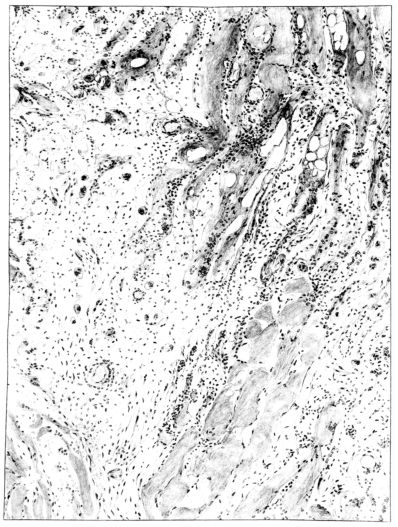

FIG. IV. AUTOPSY NO. 205. CONGESTION AND EDEMA OF THE SUBMUCOSA AND REGENERATION OF THE TRACHEAL EPITHELIUM.

The changes are less marked, perhaps, in the trachea than in its finer ramifications. The mucosa is constantly more or less destroyed and large areas, usually focal, are entirely devoid of their epithelial covering. This is replaced by a sparse exudate, composed largely of red blood cells, mucus, a small amount of fibrin, and nuclear fragments (Fig. II). It may dip into the submucosa for a short distance, but usually these indentures are associated with the ducts of the mucous glands into which the inflammatory reaction extends. A more striking feature than the exudate, however, is the edema and the congestion of the submucosa. The loose areolar tissue of the submucosa is spread widely apart, and throughout it distended blood vessels are very conspicuous. Occasionally such a vessel is broken and actual hemorrhage appears in the submucosa. Occasionally, too, the inflammation extends down the duct to the mucous gland itself, and here, also, aplastic inflammatory reaction is evident, inasmuch as the acini now stain intensely red with the cells undifferentiated from each other and specked here and there by broken remains of the dead nuclei (Fig. III). After the disease has continued for a short period, even at the end of five or six days, some regeneration of the epithelial lining may be seen (3) (Fig. IV). But despite this, the acute picture persists, and there goes on, side by side, an attempted repair characterized by epithelial regeneration and the same evidence of acute change. Since the lesion is essentially a superficial one, scars or contractures of any extent are not encountered in the trachea, even in examples of the disease that have ended fatally only after many weeks.[4]